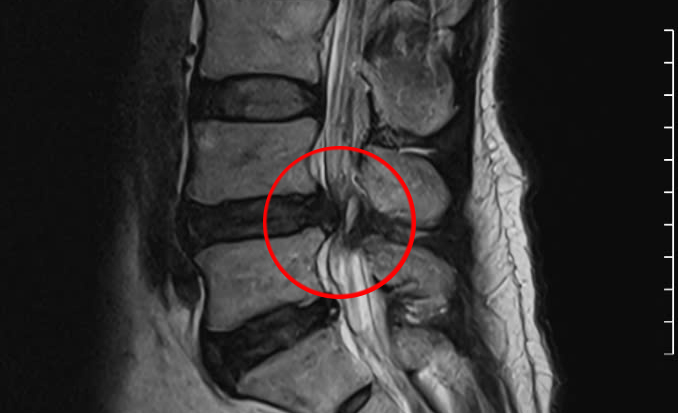

Chụp MRI cho thấy vị trí đốt sống bị trượt chèn ép dây thần kinh của người bệnh. Ảnh: Bệnh viện Đa khoa Tâm Anh

Ông Tân được chuyển vào Bệnh viện Đa khoa Tâm Anh TP HCM trong tình trạng đau không kiểm soát được bằng thuốc giảm đau thông thường,mất cảm giác vùng đáy chậu và suy giảm khả năng cử động các ngón chân,phản xạ gân gót chân suy giảm rõ rệt và có dấu hiệu tiểu khó. Kết quả chụp CT 1975 lát cắt,phát hiện đốt sống L4 trượt về phía trước,chèn ép dây thần kinh vùng thắt lưng.